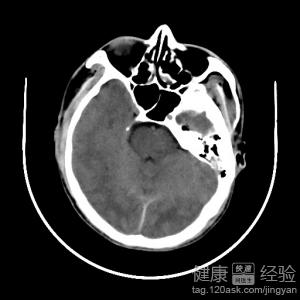

彌漫性軸索損傷也是一種很常見的疾病,主要就是因為頭部受到了損傷後而引起的一種疾病,這種疾病主要分布於腦白質就是以軸索損傷為主要的一種病變,在患了這種疾病的時候因為發病的位置不同,所以患者表現的症狀也是不一樣的,在患了這種疾病的時候一定要及時的檢查跟治療,這種疾病要是不急說的進行治療會給患者的生活帶來很嚴重的影響,下面我們就來詳細的了解下這種疾病的一些情況。

1引起這種疾病最主要的原因就是因為腦部受到了損傷而引起的,有的時候這種疾病也有可能是因為腦部組織發生了病變而引起的,患了這種疾病的時候患者的腦部神經軸索跟小血管也會受到損傷的。